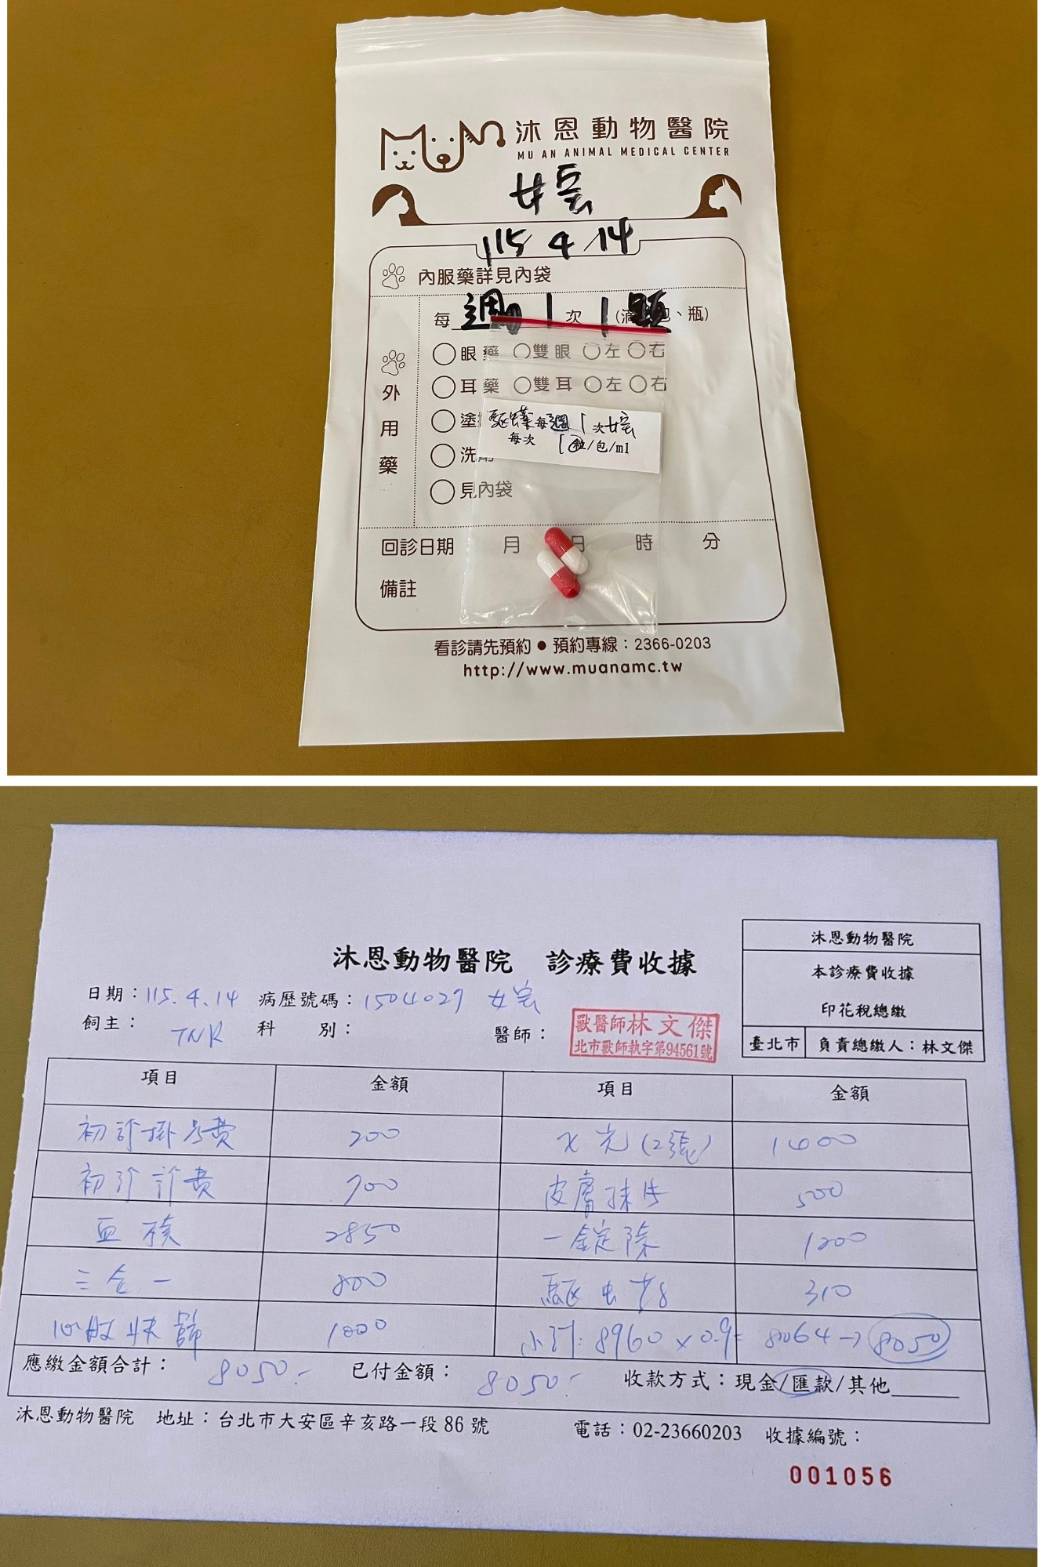

經X光檢查發現右前肢骨骼退化較嚴重,左邊也有一點骨骼退化;肺功能也是偏差;有牙周炎、牙齦萎縮所以齒根比較出來。X光有拍到兩顆東西,穿刺抹片檢查,淋巴細胞正常,淋巴結腫大。於醫院先點一錠除,並開立內用驅蟲藥,三個月後體外驅蟲需要再做一次。目前已於14日當日就醫後先行安置於協會幾日,因考量女寶年齡已大,汐止愛媽會帶回家中安置給女寶一個長久安穩的家。本筆醫助是女寶2026年4月14日於沐恩醫院看診的費用,包含血檢、X光、三合一、心臟快篩、皮膚抹片、一錠除滴劑及驅蟲藥。

今天點一錠除,三個月後體外驅蟲需要再做一次。

1.一錠除:3個月後一次。

2.驅蟲藥:一週一次每次半顆。(先吃兩次)